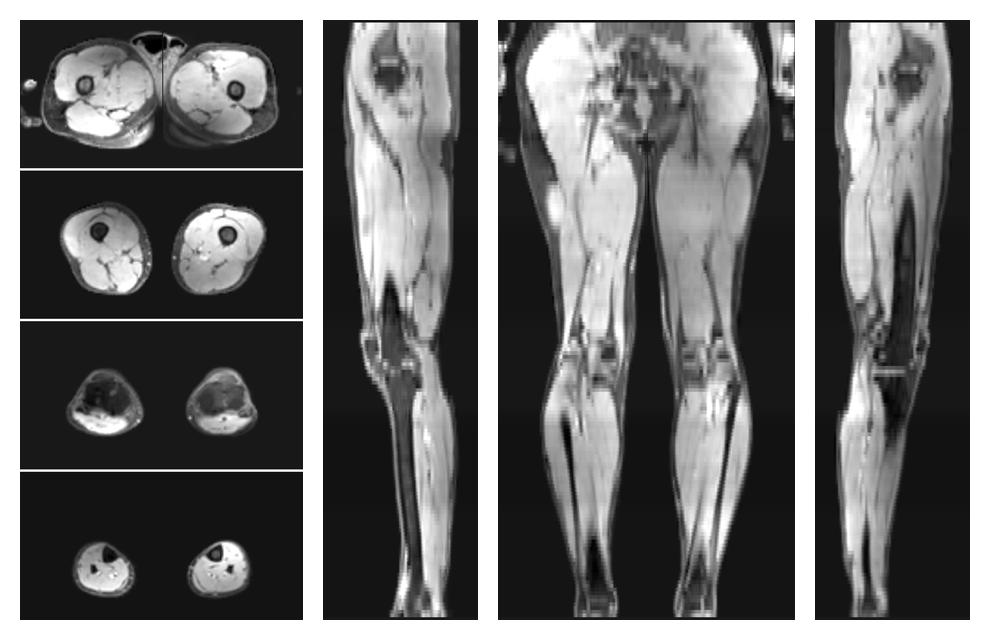

• Water only signal

The water part of the acquired multi-echo spin echo data.